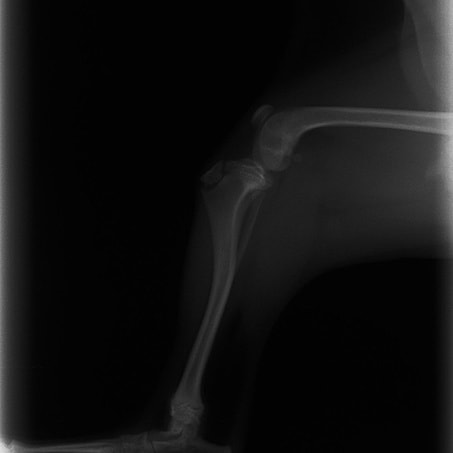

症例3:キルシュナーワイヤーのピンニングによる整復

ペルシャ猫 11ヶ月齢 雄

他院にて左大腿骨遠位の成長板骨折(salter-harrisⅠ型)が認められており、治療相談を目的として来院。当院にて、キルシュナーワイヤーを用いたピンニングにより骨折部位の整復を行いました。術後の経過は良好で、現在も経過観察中です。

術前レントゲン

術後レントゲン